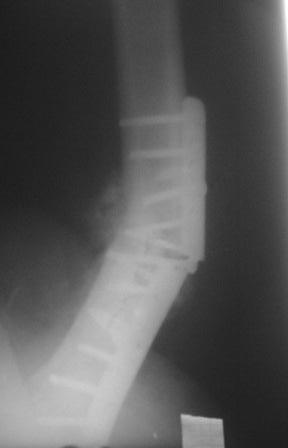

Обратился больной 54г. Травму получил в ноябре 2007г. Оперирован в

Алмате (Казахстан). Через 2 мес. гипс снят, потом еще гипс на 2

месяц, с тех пор ходит двумя костылями, последние время беспокоит

усиливающаяся боль и деформация.

Локально: укорочение ноги на 3,5см, умеренная отечность и вальгусная

деформация, умеренная болезненность, патологической подвижности почти

не определяется, но имеется наружная ротация конечности на 15гр.

Наш план БИОС, но так как при удалении пластини зона ложного сустава

открывается, для уверенности производить костную пластику (аутографт

или хотя-бы по Хахутову) ??, еще как устранить ротацию?